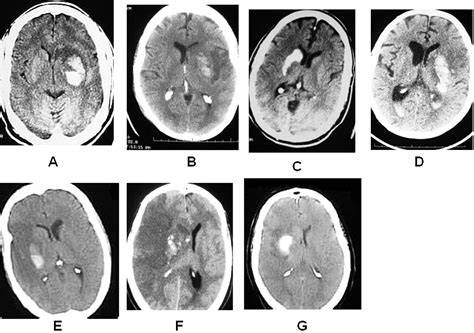

The human brain is a dynamic organ that undergoes various changes throughout a lifespan. Parenchymal volume loss, or cerebral atrophy, is essentially the loss of neurons and the connections between them. As the brain loses these cells, the physical space they occupied diminishes. This can manifest as an expansion of the sulci (the grooves on the surface of the brain) or the enlargement of the ventricles (the fluid-filled spaces inside the brain).

When a radiologist identifies volume loss, they usually assess the distribution of the atrophy. Generalized atrophy refers to widespread loss across the entire brain, while focal atrophy suggests that specific areas, such as the hippocampus or the frontal lobes, are being disproportionately affected. The following table provides a snapshot of how medical professionals categorize these findings:

Finding Typical Clinical Context

Mild/Age-Appropriate Normal aging process, minimal cognitive decline.

Focal Atrophy Potential early-stage neurodegenerative markers.

Generalized/Rapid Requires workup for systemic, metabolic, or advanced disease.

Asymmetric Loss Often seen in post-stroke changes or specific dementias.